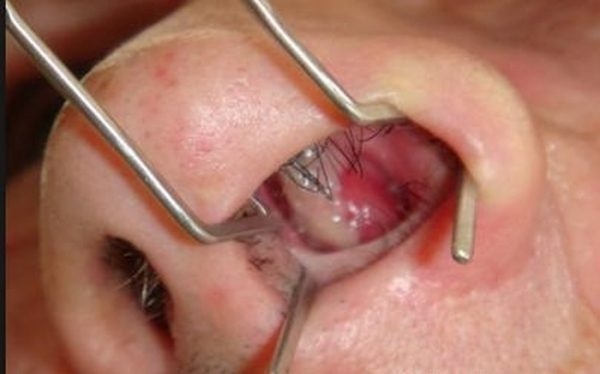

Polyp mũi gây chặn đường thở, ngạt mũi, dị hình mũi

– Polyp dạng sợi: Polyp màu trắng xám, bề mặt nhẵn, khó chảy máu hơn. Polyp mũi dạng này thường xuất hiện do xoang sàng, một số khối polyp mũi xuất hiện từ xoang hàm trên, ở vị trí sau mũi gọi là “polyp sau lỗ mũi”. Polyp này phát triển, kích thước tăng rất nhanh, lâu ngày không điều trị có thể khiến cho sống mũi to và thành thành chứng “mũi ếch”.

– Polyp dạng nhầy: Bề mặt polyp có hình giống như một quả nho đã được lột vỏ hoặc thịt của quả vải tươi, bề mặt trong và nhẵn, màu hồng nhạt, có thể hình thành một dải mỏng từ trong ống mũi, hoạt động mềm mại, linh hoạt.

– Polyp mũi dạng xuất huyết (thường ít gặp): Polyp có bề mặt trơn bóng, xuất huyết, do mềm nên rất dễ chảy máu.